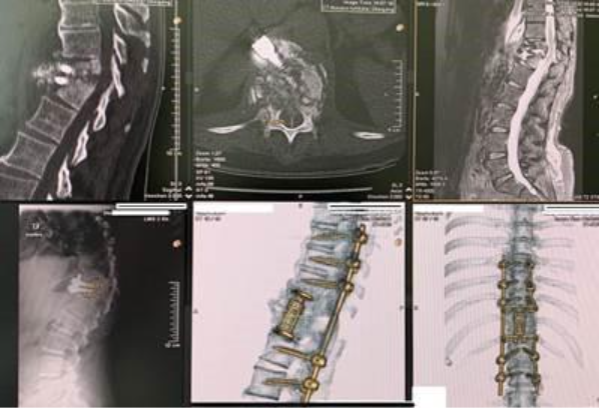

A patient underwent a thoracoscopic disc surgery at the level Th11/12 in another clinic. Shortly after the procedure, she developed severe back pain accompanied by progressive weakness in both legs and loss of bladder control.

In response to the worsening symptoms, a stabilization procedure of the affected spinal segment was performed at the same clinic. However, despite the additional surgery, the patient’s neurological condition continued to deteriorate.

She was subsequently referred to our clinic as an emergency case. Advanced imaging and laboratory investigations revealed a severe postoperative infection at the Th11/12 level involving the previously implanted instrumentation.

After careful imaging evaluation and meticulous surgical planning, we performed revision surgery. During the procedure, the infected implants were removed and the infected portions of the spine were carefully debrided using minimally invasive surgical techniques. The spine was then re-stabilized to restore structural integrity and protect neurological function.

Following surgery and appropriate medical treatment, the patient showed significant neurological recovery. She was able to walk independently again and regained a substantial degree of bladder control, with marked improvement in her overall condition.

This case demonstrates the importance of early recognition and specialized management of postoperative spinal infections, as well as the effectiveness of modern minimally invasive revision techniques in restoring spinal stability and neurological function.